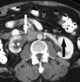

Extension of retroperitoneal mass

Posterior mediastinal lesion